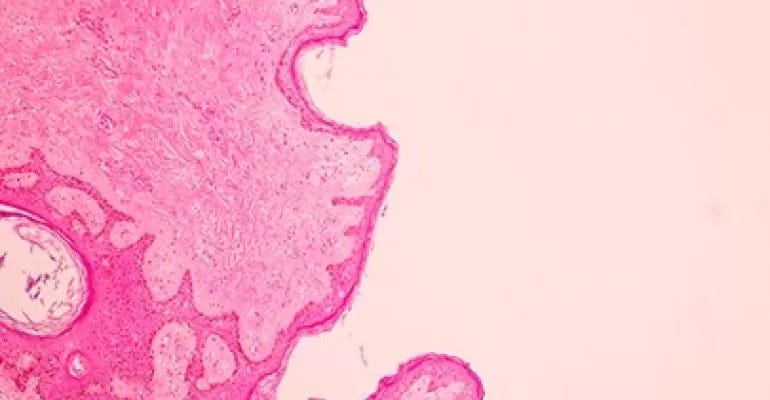

However, according to Dr. Lavina Verma, who is a specialist radiologist at Aster Clinic Bur Dubai, UAE, there are some shortcomings faced when mammography is used as the only radiological tool in order to assess a patient’s risk for breast cancer. “One of the primary reasons for the shortcomings is the presence of dense breast tissues (parenchymal tissue) in the breasts of some patients, which has resulted in false negative results (15 to 20 per cent) of mammograms for those patients that have dense breasts,” she explains.

DBT or 3D-mammography, is a mammography technique in which multiple mammographic images are acquired of compressed breast from multiple angles by using low dose x-rays and are then reconstructed into overlapping thin slices that can be displayed either individually or in a cine loop. The radiation dose received when DBT is combined with conventional 2D mammography is nearly double that of digital mammography alone, but within the established and acceptable safe dose.

“Ultrasound and Magnetic Resonance Imaging (MRI) are two supplementary breast imaging modalities that retain their sensitivity in women with dense breasts, and when used in addition to mammography, can demonstrate an increased cancer detection rate compared to mammography alone,” adds Dr. Verma. “Elastography is another test that can be done as part of an ultrasound exam and is useful in revealing if the area is more likely to be cancerous or a benign (non-cancerous) tumour.”

Assessment and diagnostic work up of screen-detected abnormality is best achieved using the triple assessment: 1. Imaging; usually diagnostic mammography and ultrasound; 2. Clinical examination; and 3. Image-guided needle biopsy for histological examination, if indicated.